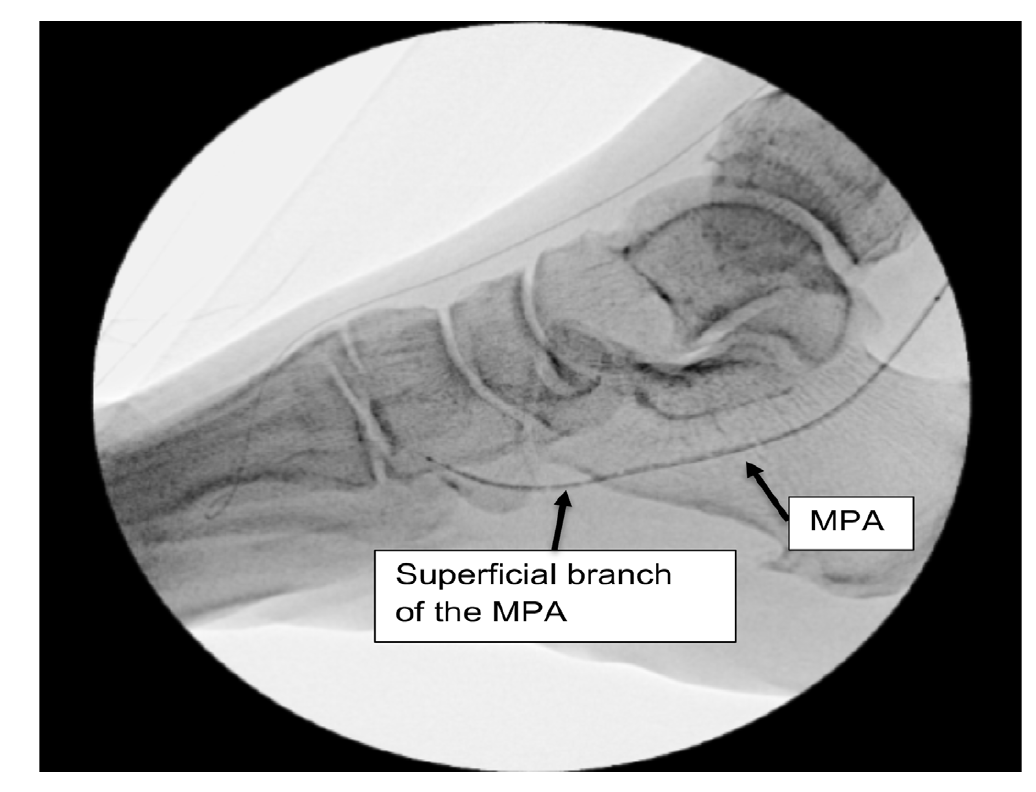

However, the entirety of the medial plantar artery (MPA) distribution was chronically occluded shortly after take-off (Figure 2E and Figure 2F). Super-selective angiography revealed chronic total occlusion of the medial branch of the first common plantar digital artery arising from the first plantar metatarsal artery (Figure 2G). Angiography also revealed an occluded accessory branch arising medially from the superficial branch of the MPA.

The anatomy of the arteries supplying the hallux is complex, with variants being common. In this patient, an atypical accessory branch arising from the superficial branch of the MPA was present. While the arterial anatomy of hallux-supplying arteries and its corresponding variants are not readily discussed in recent literature, certain textbooks do depict an accessory branch arising from the superficial branch of the MPA.2 The accessory branch of this patient, in particular, communicated with the first dorsal metatarsal artery arising from the DPA (Figure 2F) and the superficial branch of the MPA communicated with the medial branch of the first common plantar digital artery arising from the LPA (Figure 4C). In general, using the angiosome concept, the blood supply to the hallux consists of 3 main avenues: (1) the first dorsal metatarsal branch arising from the DPA; (2) the plantar digital arteries arising from the first plantar metatarsal artery, which is a branch of the LPA; and (3) the superficial branch of the MPA.3,4 The latter 2 sources of blood supply were absent in this case.